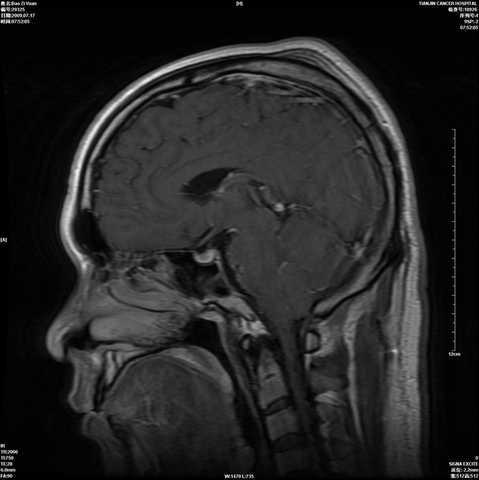

海绵状血管瘤:

手术前